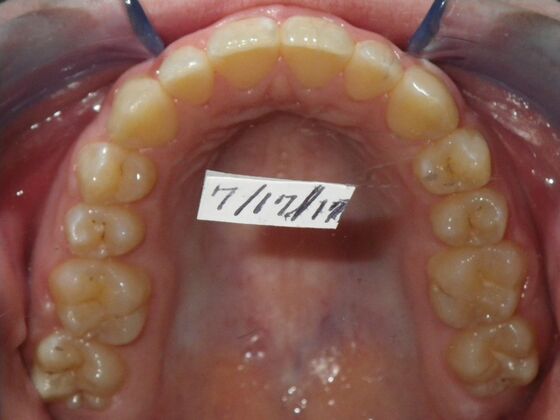

This case presents with a dental midline discrepancy. The upper incisors are tipped toward the palate, which prevents the lower incisors from establishing proper arch form. The upper right molar has drifted forward, causing the upper midline to be skewed to her left. By distalizing the upper left molar, we can correct the midline discrepancy. Lastly, both upper and lower arches need expansion. All of this was completed with conventional straight wire appliances within 2 years.